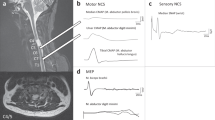

MEP response to bifocal transcranial magnetic stimulation was evaluated bilaterally in the rectus femoris muscles. TMS was performed using a 7-cm diameter coil from MagVenture A/S, Denmark (MagPro 100), and navigation-guided TMS (Brainsight Frameless 1.5, Rogue Research Inc., Montreal, Canada) was used to determine the optimal position of each stimulation point (stimulation hot spots), starting about 4 cm rostral to Cz (vertex).13 TMS was delivered every 5–6 s. The duration of the monophasic transcranial single-pulse stimulus was 100 μs, the sample frequency was 2000 Hz, and a band-pass filter was set at 30 Hz–1 kHz. When the patient was unable to produce force, he was asked to exert as much volitional stimulation as possible. If there was a well-defined response, 3–5 representative MEPs at the desired stimulus intensity were recorded, and when there was a visible but poorly defined muscle response, up to 10 stimuli were delivered in order to realize three responses that could be stored offline for further analysis.14,15 The onset of the fastest response from four repeated MEP trials was identified as the onset latency, MEP amplitude was calculated from baseline to the negative peak for the largest response out of four trials, and the intensity of the magnetic stimulus was expressed as a percentage of the maximal stimulator output.

At 12 weeks, the quadriceps, hamstrings, anterior tibialis and gastrocnemius muscles produced EMG responses during the leg-upward task. By 36 weeks, the patient was able to crawl on his hands and knees and at 48 weeks he was ambulating with long leg braces and Lofstrand crutches. We did not detect EMG signals in the leg during walking, but we did detect EMG signals bilaterally upon voluntary contraction of the quadriceps, hamstrings, anterior tibialis, gastrocnemius, gluteus and thenar muscles (Figure 3).

The patient received EMG biofeedback training and practiced knee walking in a warm-water pool from weeks 48 to 96 after transplantation. The goal of the EMG biofeedback training was to identify triggers of voluntary action by detecting neuromuscular contractions and providing feedback signals to the patient in order to establish learned voluntary control.16 During this training, surface electrodes were placed over the quadriceps muscles and the patient was instructed to attempt knee extension while watching the EMG signals on a monitor. By 96 weeks, he was able to extend his knees on his own and to walk on his knees in the parallel bars, and MEPs were elicited in both quadriceps muscles at 96 and 144 weeks, respectively (Figure 4). The patient used iliopsoas for thigh flexion in the swing phase, but he did not use the hamstrings for knee flexion. He could not push off his toes because he had no use of tibialis anterior or gastrocnemius. At 144 weeks, the patient was ambulatory with short leg braces and Lofstrand crutches. The patient’s condition was documented pre- and postoperatively, and this is shown in a video recording that accompanies this report.